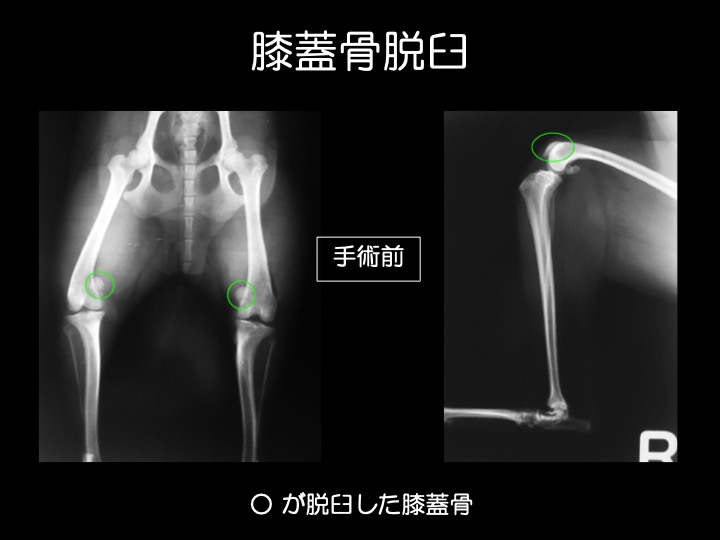

・膝蓋骨脱臼とは、後ろ足の「ひざの皿(膝蓋骨=パテラ)」が大腿骨滑車(皿の収まる溝)から外れる状態をいいます。

・外傷が原因で脱臼することもありますが、多くは先天性で成長期の異常として見つかります。トイプードル、チワワ、 柴犬などに多い疾患です。

・膝蓋骨が脱臼すると、膝をまっすぐに伸ばせなくなるため、ケンケンしたり、突然キャンと泣いて後ろ足を気にする、ガニ股に見える、などの症状がみられます。

・当院では、①明らかな症状がある場合(中等症〜重症)や、②生後6ヶ月未満の若い時期に脱臼が見られる場合(成長に伴い悪化するリスクが高い)に、治療、手術をお勧めしております。

・写真のワンちゃんのように、経過が長い子は、痛みから足を着かなくなってしまい、足全体の筋肉が徐々に痩せていってしまいます。

・外方脱臼は内方脱臼よりも痛みが強く出る傾向があり、跛行などの症状も顕著です。